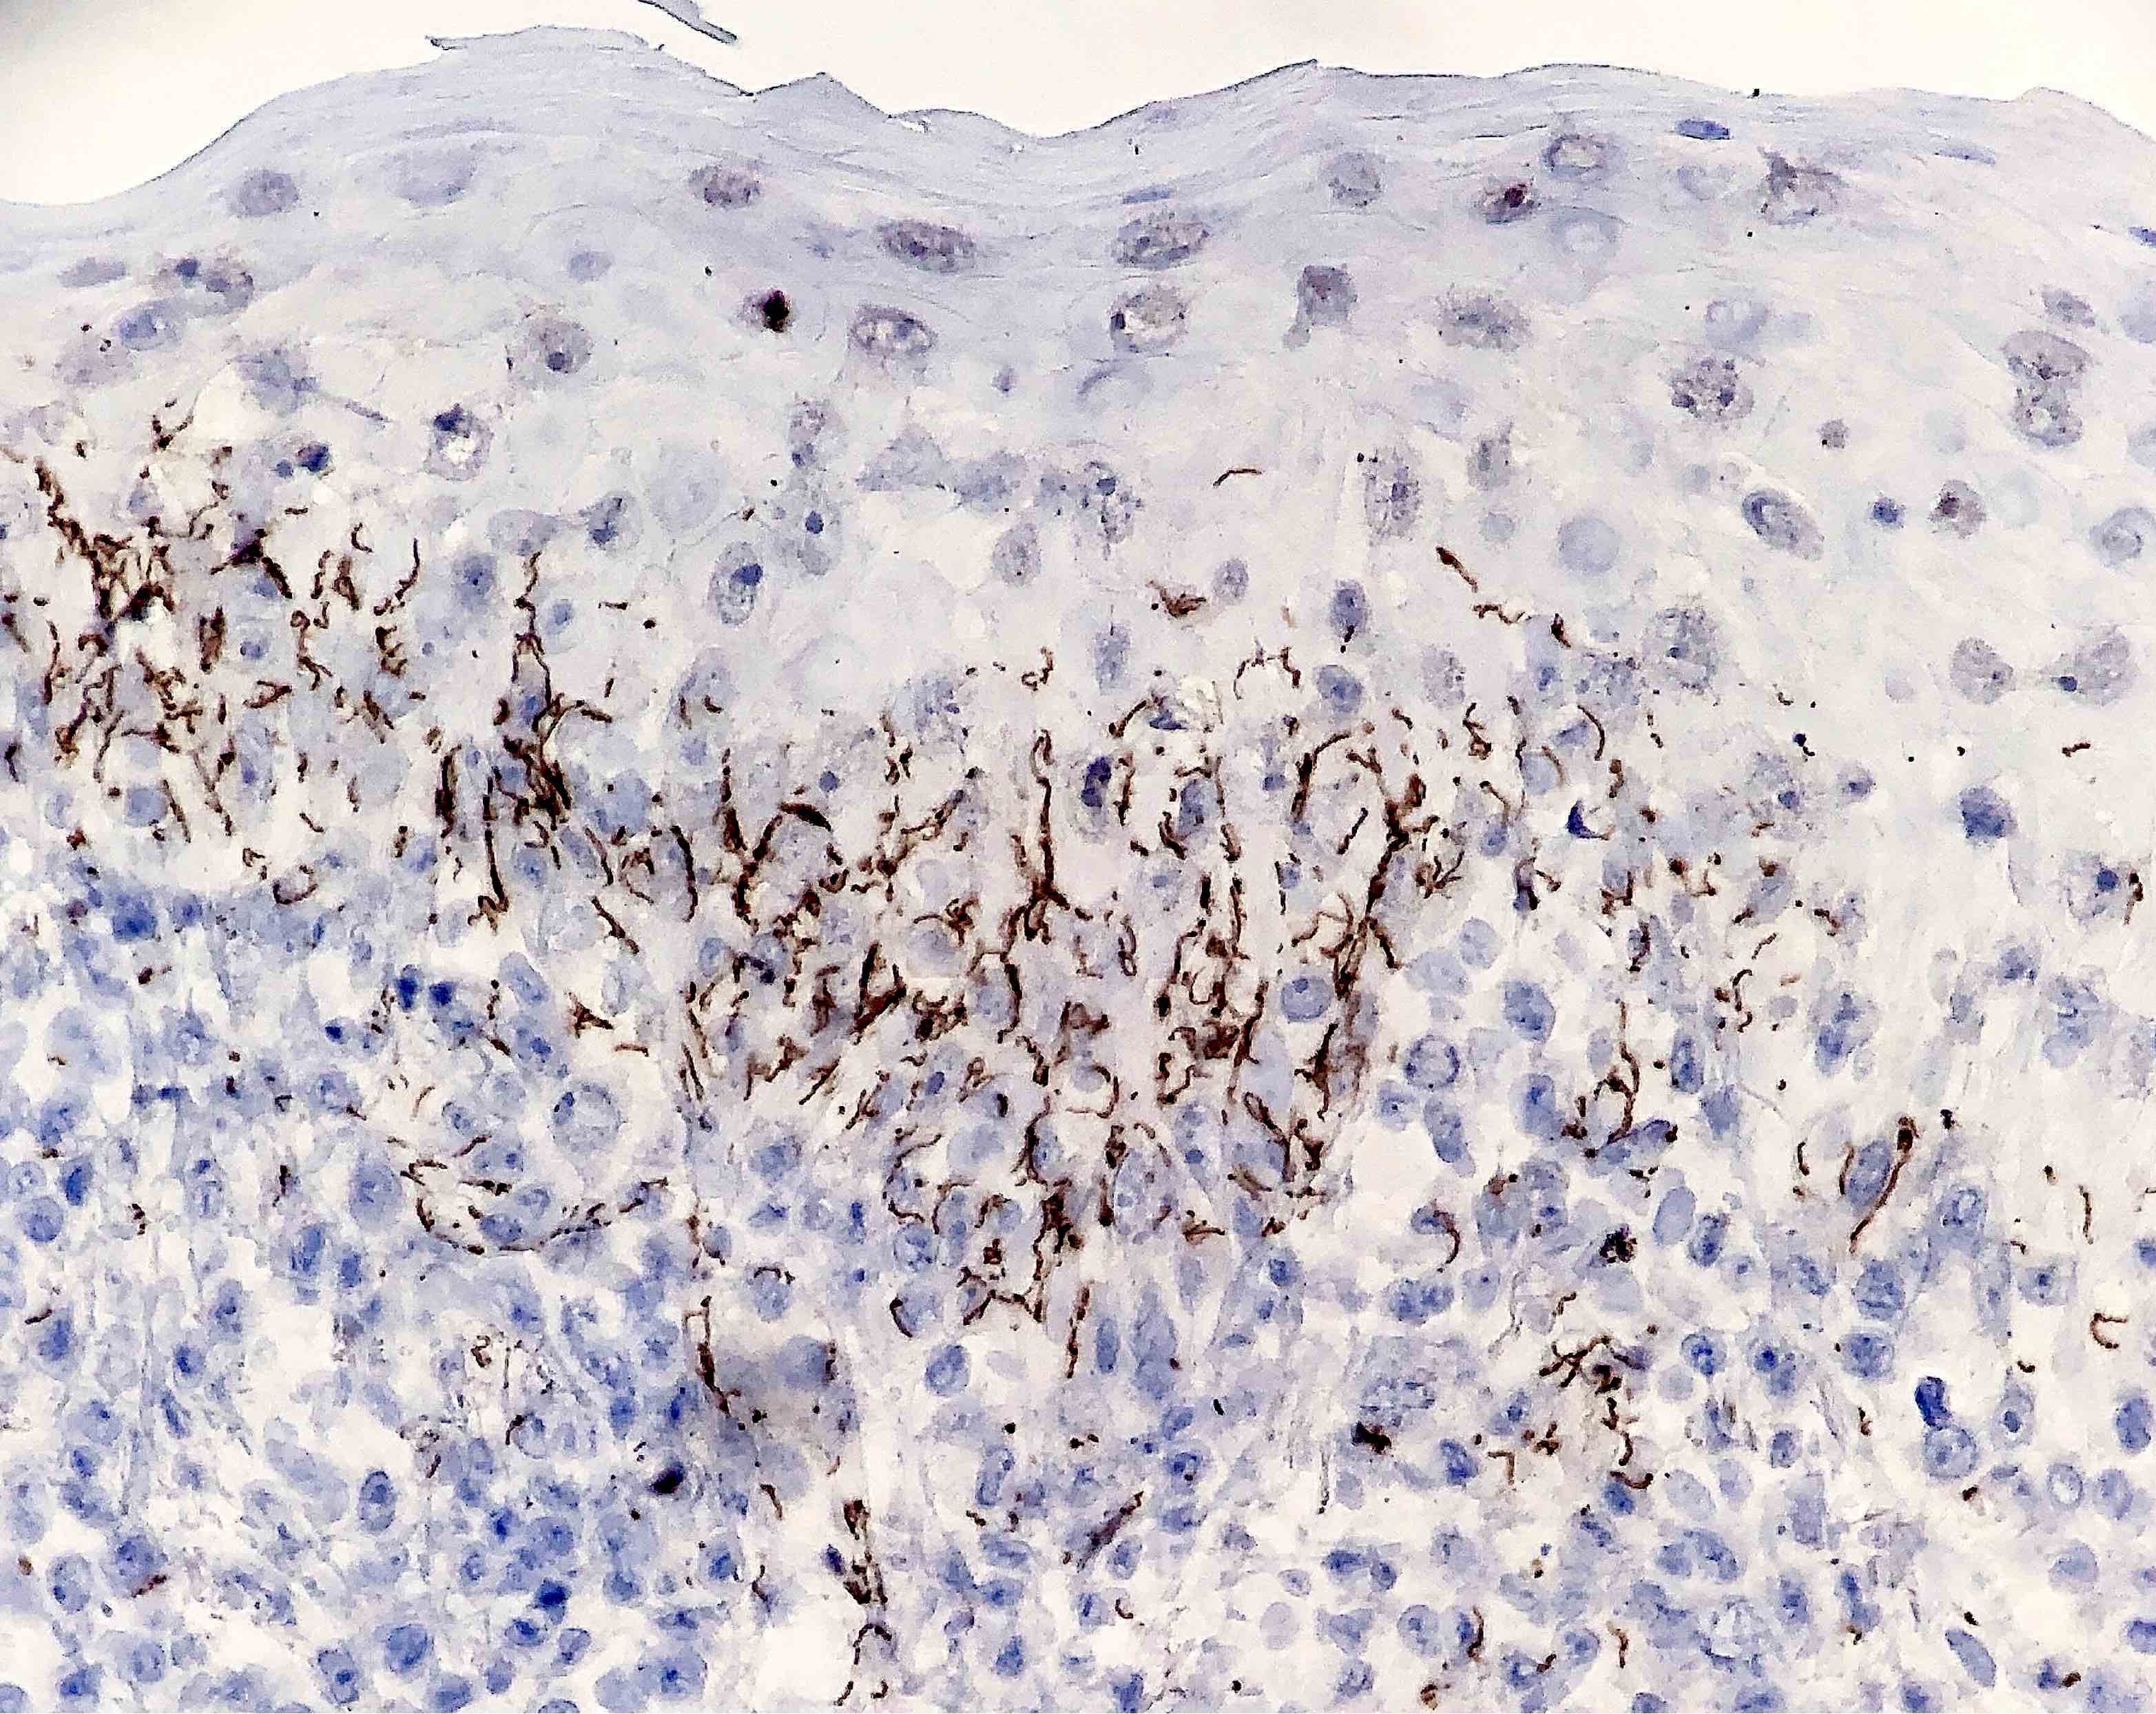

Microscopic (histologic) images

Contributed by Silvija P. Gottesman, M.D., Hillary Rose Elwood, M.D., Mark R. Wick, M.D. and AFIP images

Positive stains

- Silver stains: Warthin-Starry or Steiner stain (41% sensitive) (J Cutan Pathol 2004;31:595)

- Immunohistochemical stain: treponema (71% sensitive) (J Cutan Pathol 2004;31:595)

- Comment: There is psoriasiform epidermal hyperplasia with superficial and deep perivascular lymphohistiocytic infiltrate. Admixed plasma cells are also noted. The infiltrate forms a band beneath the hyperplastic epidermis and envelopes some of the adnexal structures. Endothelial swelling of the superficial vascular plexus is present. A treponemal immunohistochemical stain shows numerous coiled spirochetes in the lower half of the epidermis. These findings are diagnostic of syphilis.